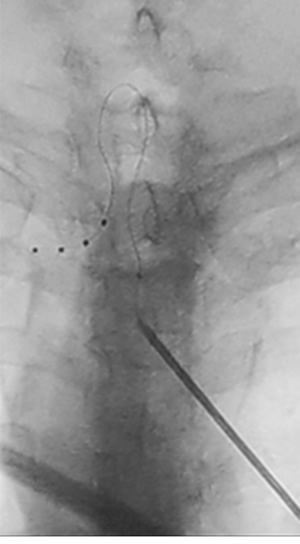

Figura 1

Tabla I

Figura 2

Figura 3

Figura 4

Figura 5

Figura 6

Figura 7